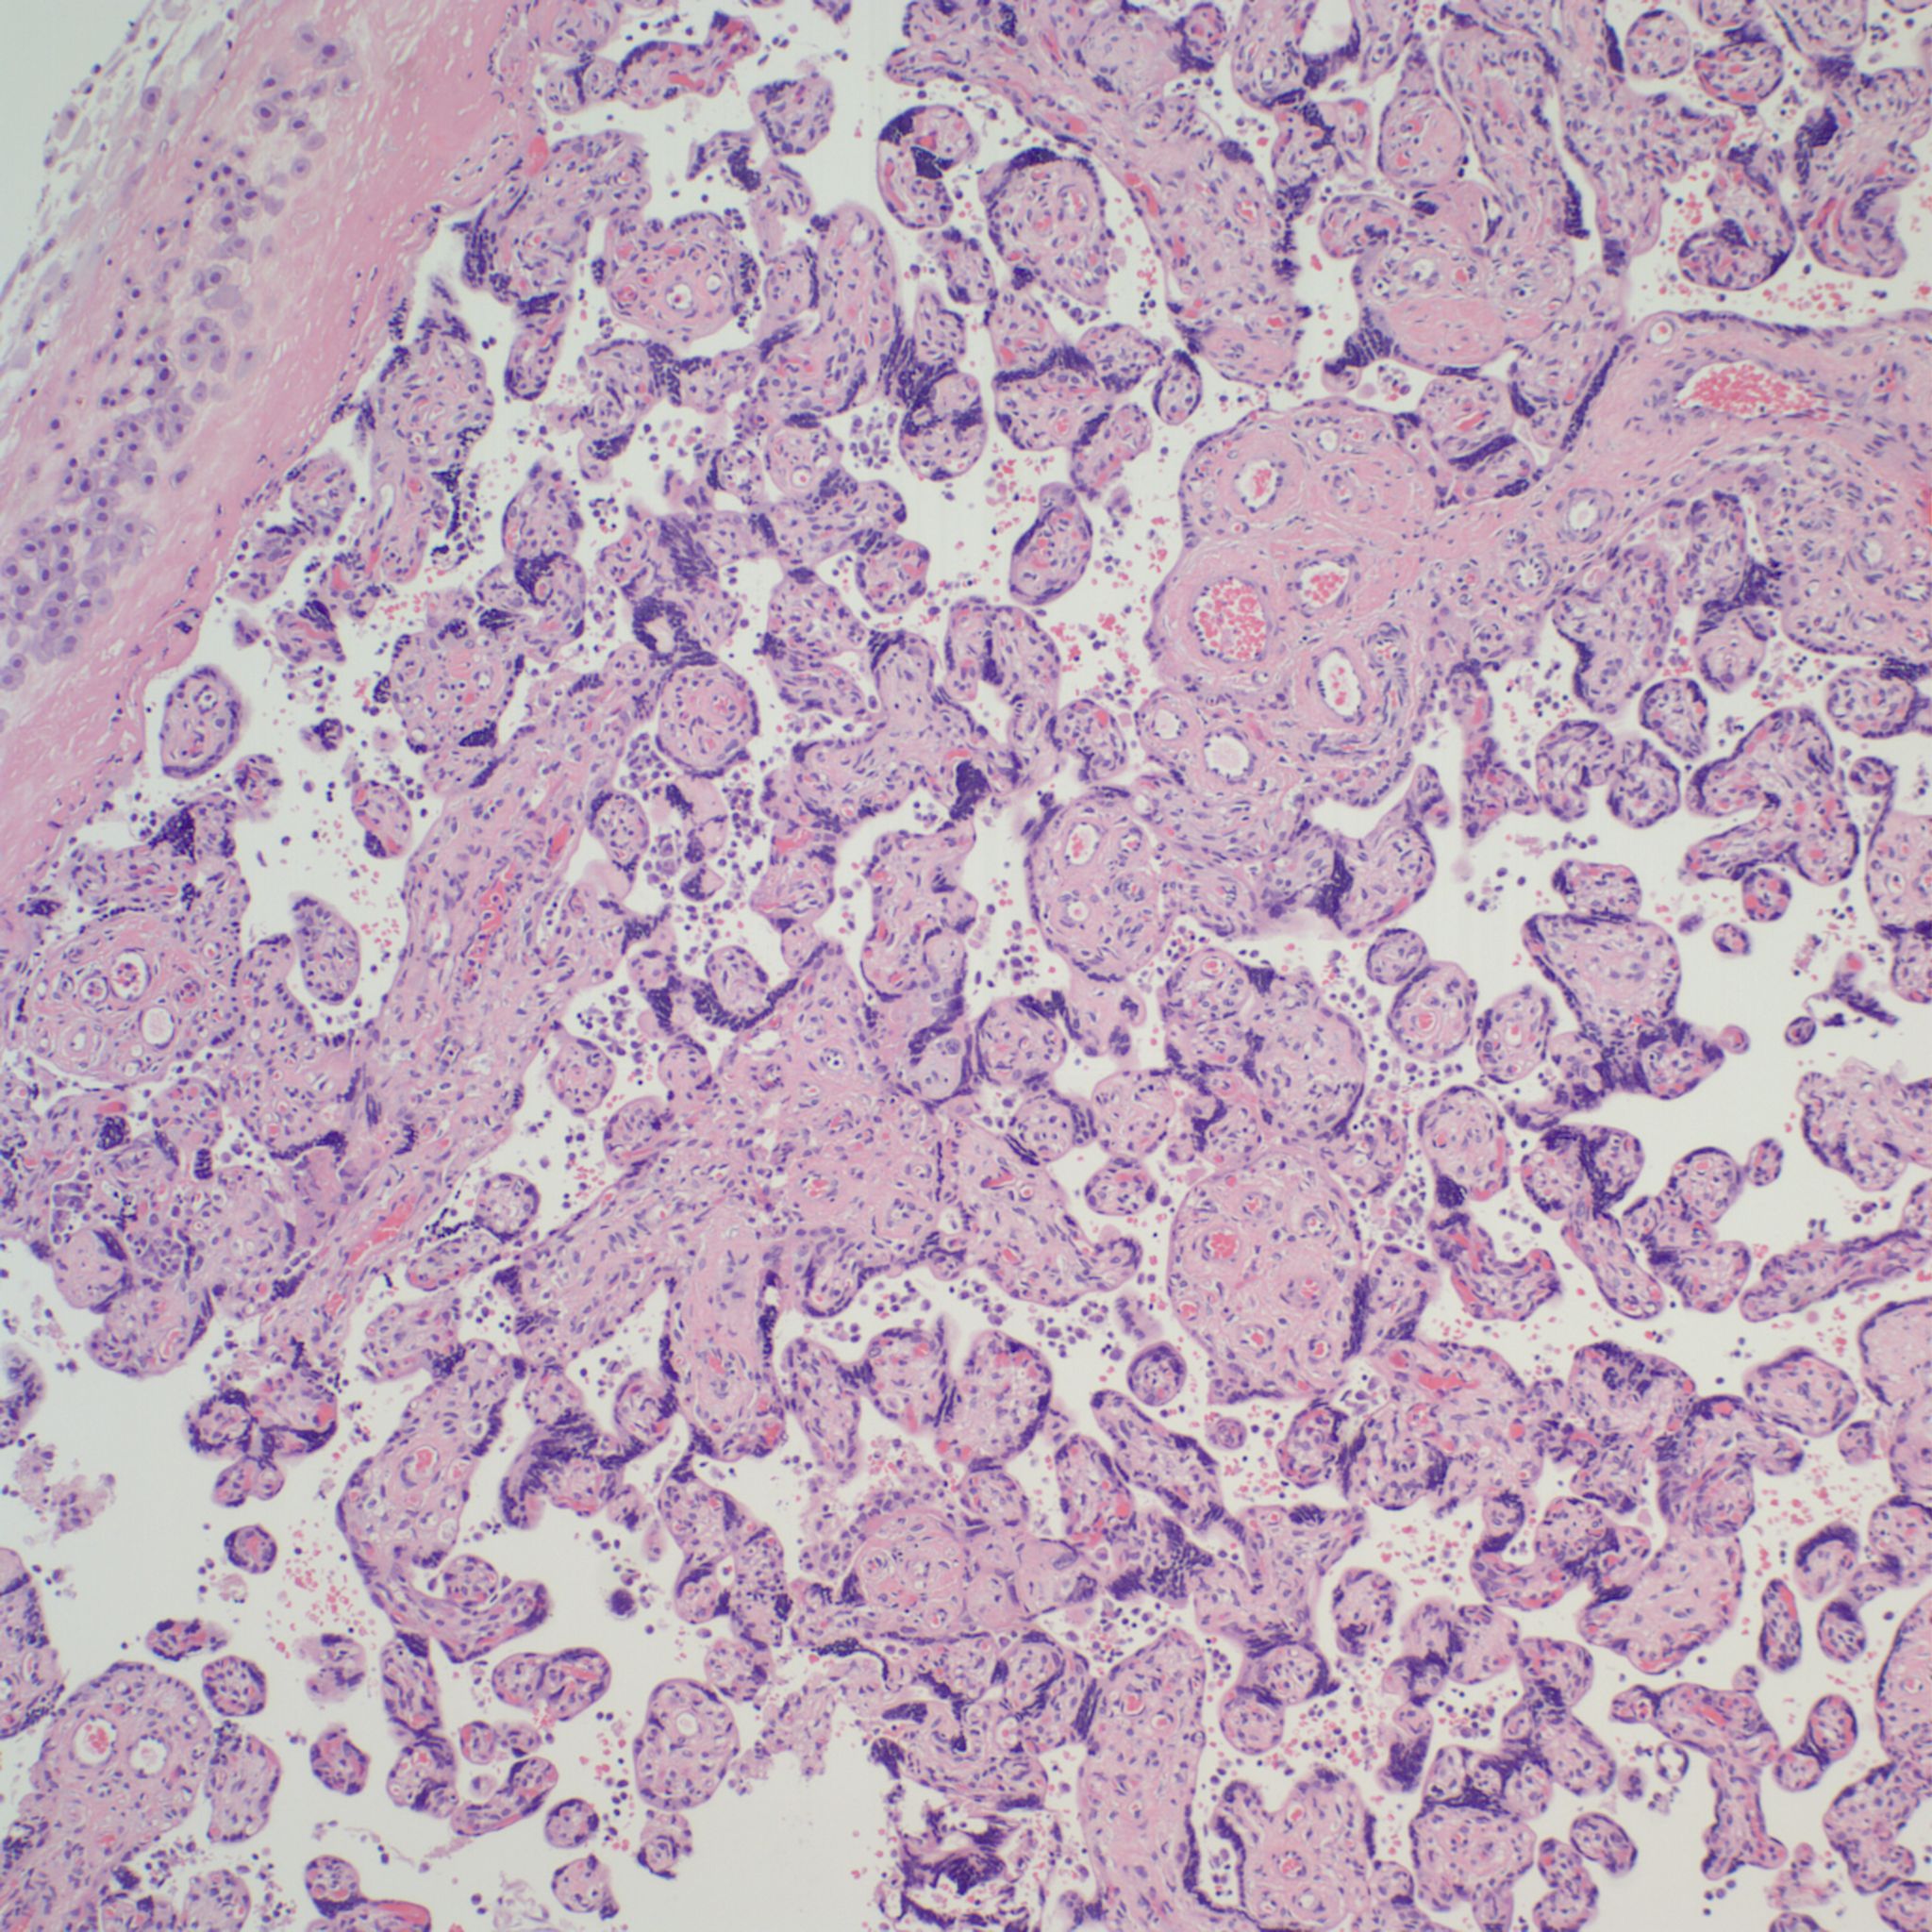

High Grade (massive) CHIV

Microscopic criteria: The primary criterion is monocytes clustered in the intervillous space which can be confirmed by CD 6810,17. The monocytes often have kidney bean shaped nuclei and prominent cytoplasm. Some other consensus criteria are that the inflammatory cells in the intervillous space should be at least 80% monocytes, and these should be maternal cells1,17.

Extent and Severity: If this is an untreated case, one accepted criterion is that the monocytes occupy 5% of the sampled intervillous space. The severity can also be graded usually as less than versus more than 50% of the intervillous space filled with monocytes. The number of monocytes in the largest clusters, and whether the distribution is evenly distributed or focal may also be useful observations.